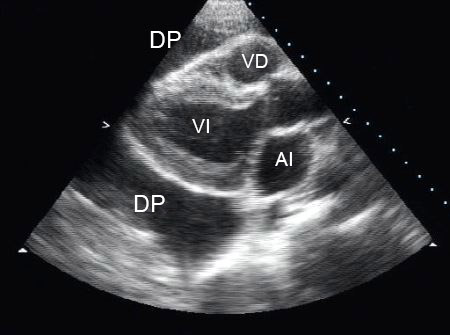

La ecocardiografía transtorácica es la prueba diagnóstica de elección para un supuesto derrame pericárdico. Es una modalidad de diagnóstico no invasiva y eficaz. Además de confirmar el diagnóstico, la ecocardiografía permite al operador evaluar el tamaño y los efectos hemodinámicos del derrame.[7]

Un espacio sin eco entre las dos capas del pericardio indica la presencia de un derrame.[Figure caption and citation for the preceding image starts]: Vista paraesternal de eje largo de un derrame pericárdico (DP); AI = aurícula izquierda, VI = ventrículo izquierdo, VD = ventrículo derechoDe la colección del Dr. Rajdeep Khattar [Citation ends].

[Figure caption and citation for the preceding image starts]: Vista apical de 4 cámaras de un ecocardiograma 2-dimensional de un paciente con derrame pericárdico tuberculoso; AI = aurícula izquierda, VI = ventrículo izquierdo, Derr. per.= derrame pericárdico; AD = aurícula derecha, VD = ventrículo derechoDe: George S, Salama AL, Uthaman B, et al. Heart. 2004; 90:1338-1339 [Citation ends].

La evaluación ecocardiográfica general de un derrame pericárdico incluye: